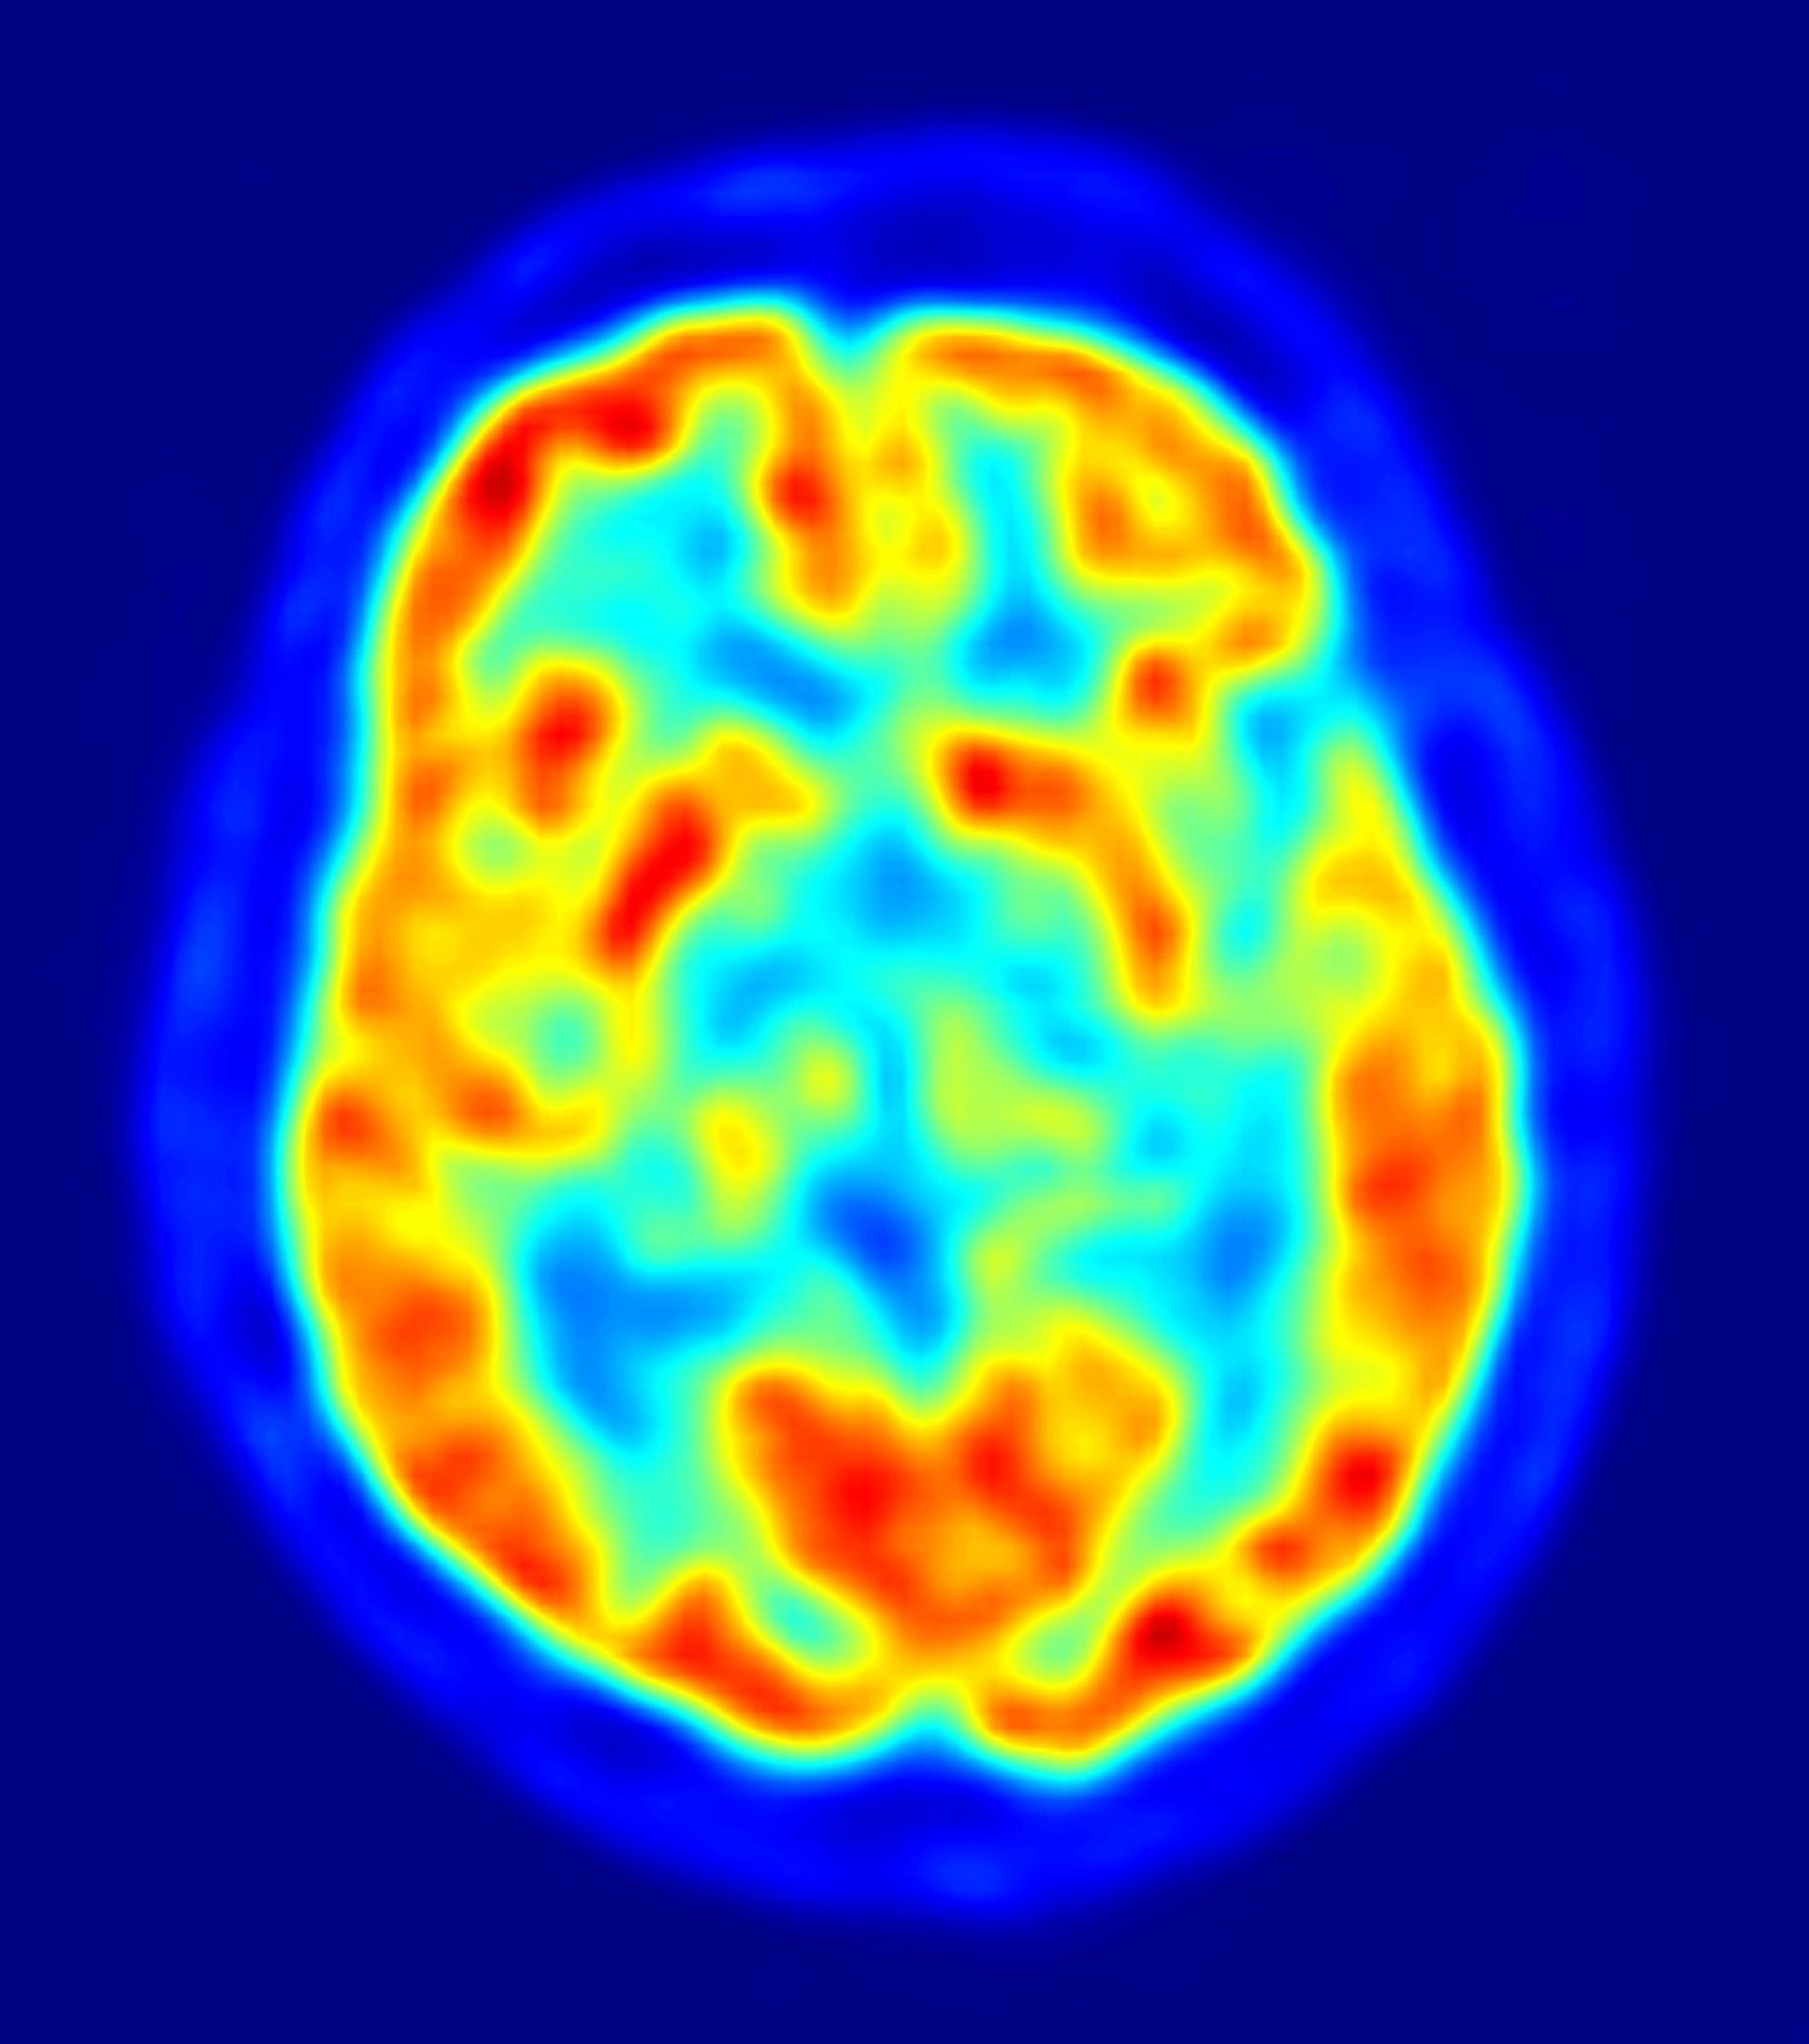

El equilibrio en las señales que emplean las neuronas consigue que el cerebro trabaje de forma correcta

Un equipo de científicos del Consejo Superior de Investigaciones Científicas (CSIC) han descubierto que el cerebro percibe de forma normal cuando existe un equilibro entre la excitación y la inhibición, dos tipos de señales que las neuronas emplean para "conversar".